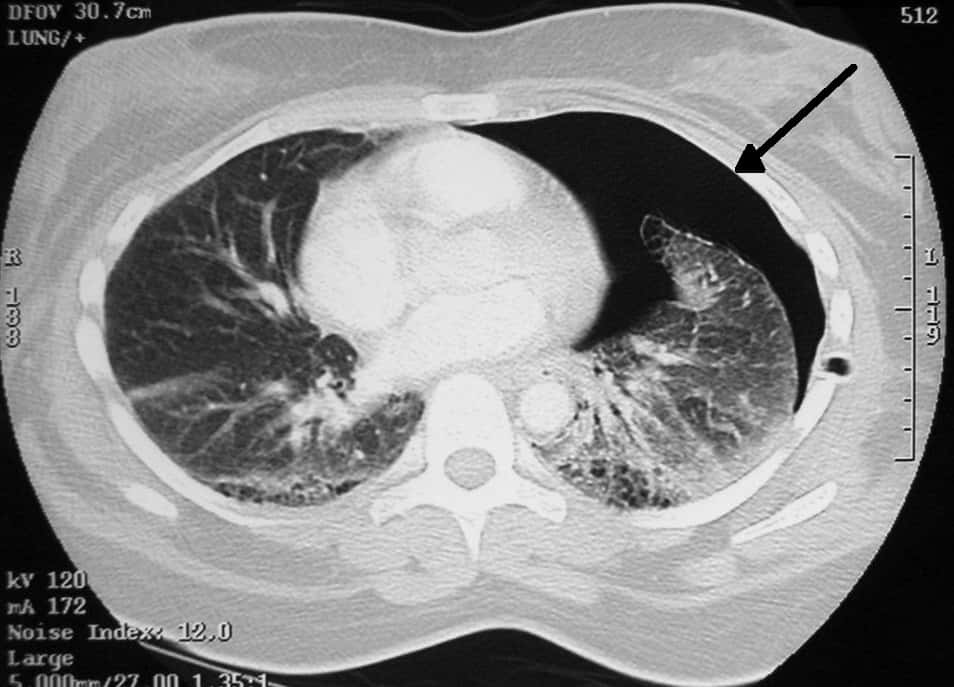

#14 A Total Yikes Moment

I'm a CT tech. I was to scan a woman's abdomen for belly pain. She and her girlfriend were there. I had to do a pregnancy test since I couldn't radiate a fetus. She denies up and down that she was pregnant, and then, after the test I did, it said she was. She denied it and demanded a blood test since she had never, ever been with a man.

Well, the blood test came back positive, and the argument that ensued was biblical. She was arguing with everyone: her girlfriend, the nurses and the doctor. I never ended up scanning her and they chalked up her pain to her being pregnant. The look on her girlfriend's face when I said it came back positive was one I will never forget.